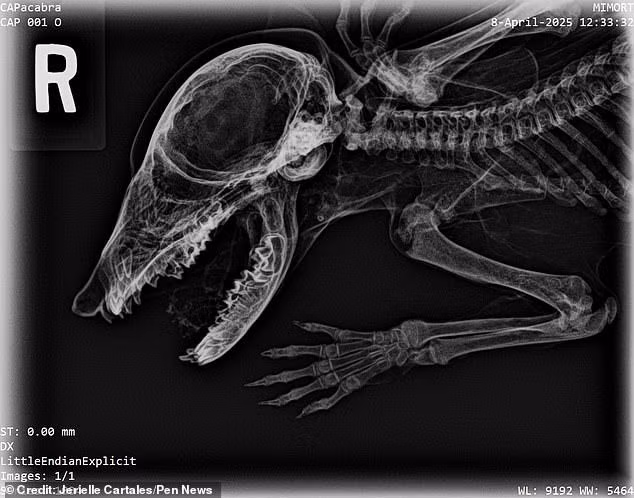

Xác ướp “Capacabra” hiện đã được chụp X-quang và so sánh bộ xương của nó với các loài khác đã biết. Theo đó, các chuyên gia loại bỏ những ứng cử viên hàng đầu như chó, mèo và chuột. Từ những đặc điểm của bộ xương, các chuyên gia suy đoán “Capacabra” có thể là một con gấu mèo. Hộp sọ và mõm của con vật này khá trùng khớp với đặc điểm của loài gấu mèo. Tuy nhiên, do xác ướp thiếu mẫu răng nên các chuyên gia chưa thể khẳng định đó có phải là một con gấu mèo hay không.